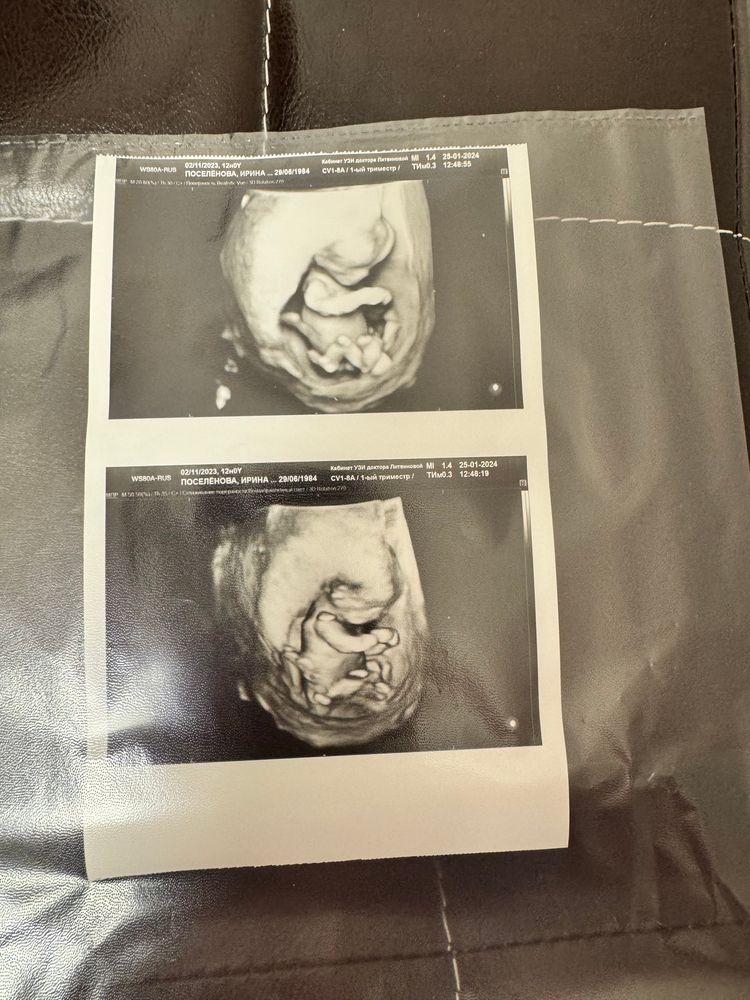

Вот и мой 1 скрининг

По показателя всё в норме, поздравляю Вас ☀️🙏 жду наш скрининг 5.02 с нетерпением. Такое фото у вас интересное, как 3d узи

Анастасия, спасибо 🙏🏻 легкой беременности ❤️ а про фото наверное это и есть 3d снимок 😁 я платно узи делала

Ирина, аа, если платно, то да, обычно скрининг не делают в 3д, если по направлению)

Я смотрела главное чтобы был нос приличный и твп маленький, ну и шейка хорошей длины. У вас все хорошо.

Всё хорошо у вашего малыша